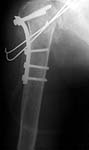

A man 47 y.o. just admitted to our unit with the fracture of proximal humerus and posterior luxation of the head. 1 month since the injury.

He was operated through extended anterior approach. Luxation of the head was reduced, the tubercle was found already united to the head. Few small fragments were removed. Transarticluar wires for 4 weeks, plaster cast to 8 weeks are planned. See attachment for images.